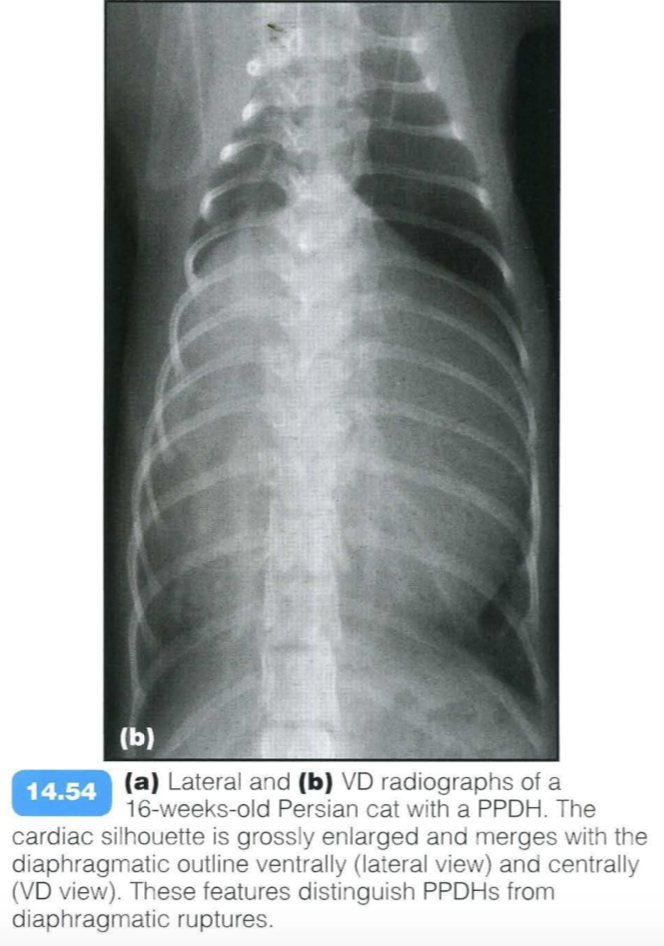

Peritoneopericardial diaphragmatic hernia (PPDH) is the most common diaphragmatic hernia in dogs and cats. It is due to an embryological fusion defect in the ventral diaphragm, leading to a communication between the pericardial and the peritoneal cavities. PPDHs are often associated with sternal or cardiac defects. The liver is the most frequently herniated organ, and may be associated with gallbladder, stomach, small intestine or omental herniation.

Clinical signs depend on the organs herniated and the size of the defect, and include respiratory, cardiovascular and gastrointestinal disorders. Auscultation may reveal muffled heart sounds or borborygmy over the cardiac area. Sudden onset of clinical signs may arise secondary to strangulation of a herniated organ. Most frequently no clinical signs are present and a PPDH is found incidentally.

Radiographic findings include: